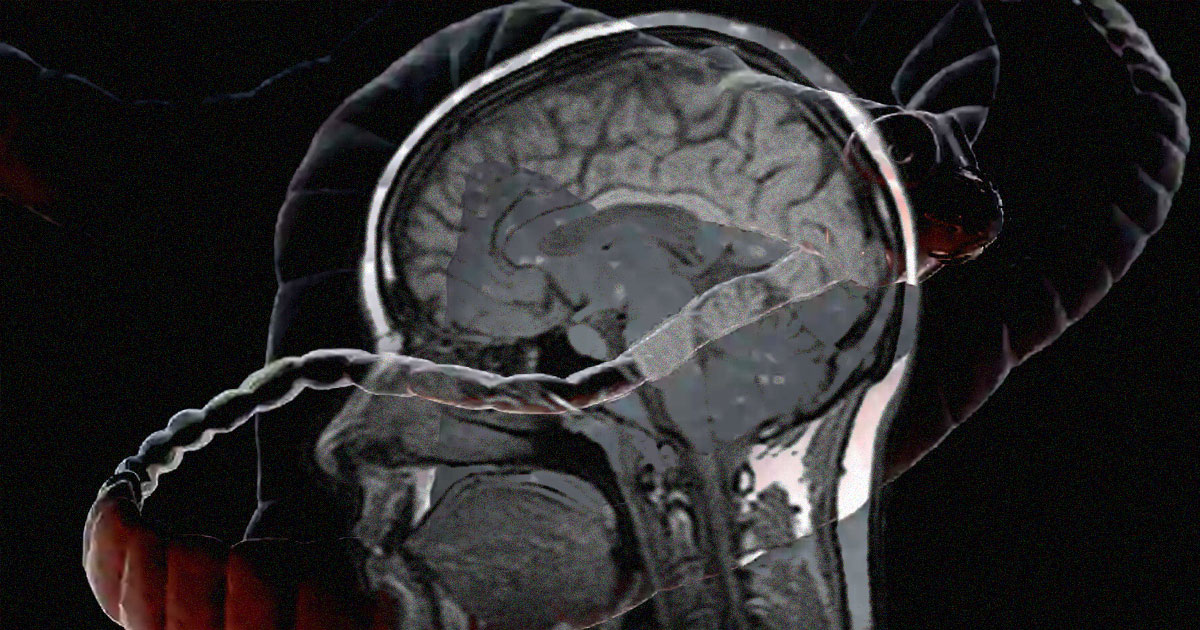

The 38 year old’s illness was initially a mystery as he seemed in otherwise good health. However, when doctors performed a CT scan on the patient’s head, they discovered three calcified lesions on his brain. Eventually, they diagnosed him with neurocysticercosis — a parasitic infection caused by larval cysts from pork tapeworms burrowing into his head years before.

Once in the brain, the larval cyst can sit for years and form a nodule, where it can eventually calcify and cause seizures.